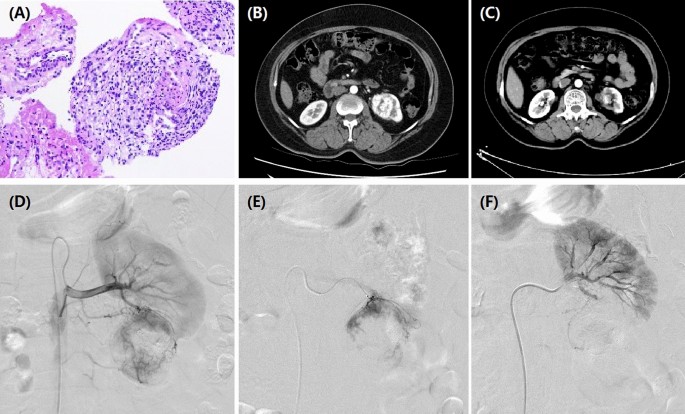

The observational study was approved by the Institutional Review Board of Zhengzhou university committee on human investigation. Written informed consent was obtained from all patients. All methods were performed in accordance with the relevant guidelines and regulations. This study was conducted in 35 patients with unresectable RCC who underwent DEB-TACE using doxorubicin-loaded CB from July 2016 to May 2020. Indications for DEB-TACE: age < 85 years; pathological confirm of RCC (Fig. 1A); recurrence or progression after operation or standard treatments; refused or ineligible to receive standard treatments due to severe visceral dysfunction; no life-threatening diseases. Exclusion criteria: with other carcinoma but receive no treatment; white blood cell count < 3.0 × 109/L; platelets count < 40.0 × 109/L; active and severe infection; breastfeeding woman; pregnant woman.

A 55-year female with left RCC treated by CB. (A) Pathological diagnosis of clear-cell type RCC in left kidney. (B) CT examination before operation revealed RCC of left kidney. (C) The left renal tumor was found to shrink after 3 months' follow-up. (D) A RCC was shown in left kidney by renal artery angiography. (E) The tumor-feeding artery was superselectively incubated via microcatheter. (F) The blood supply artery was embolized by the drug-loaded microspheres.